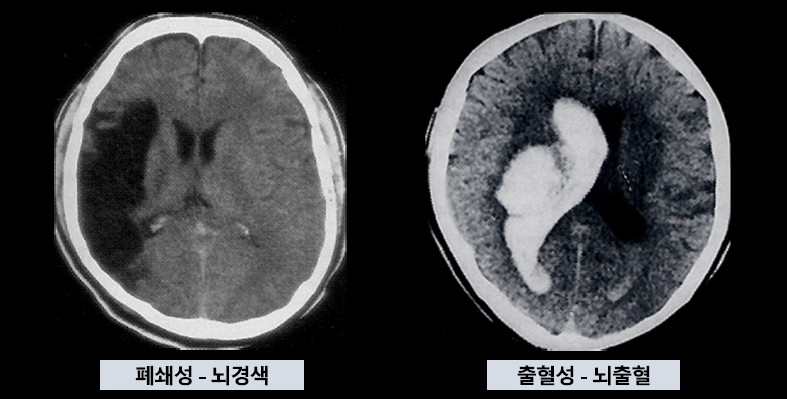

뇌경색과 뇌출혈

[에스포항병원 제공]